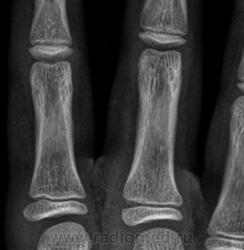

Остеоэпифизеолиз о/ф III пальца.

Спасибо Валентин Львович за обработку изображений, в данном случае остеоэпифизиолиз проксимальной фаланги 3п.. В косой проекции кстати даже четко видно ступеньку.